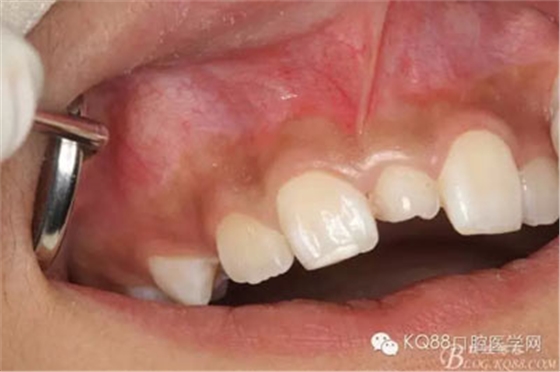

圖1.術(shù)前患者的口內(nèi)照片,11和 21之間有一多生牙,牙冠形態(tài)尚可。